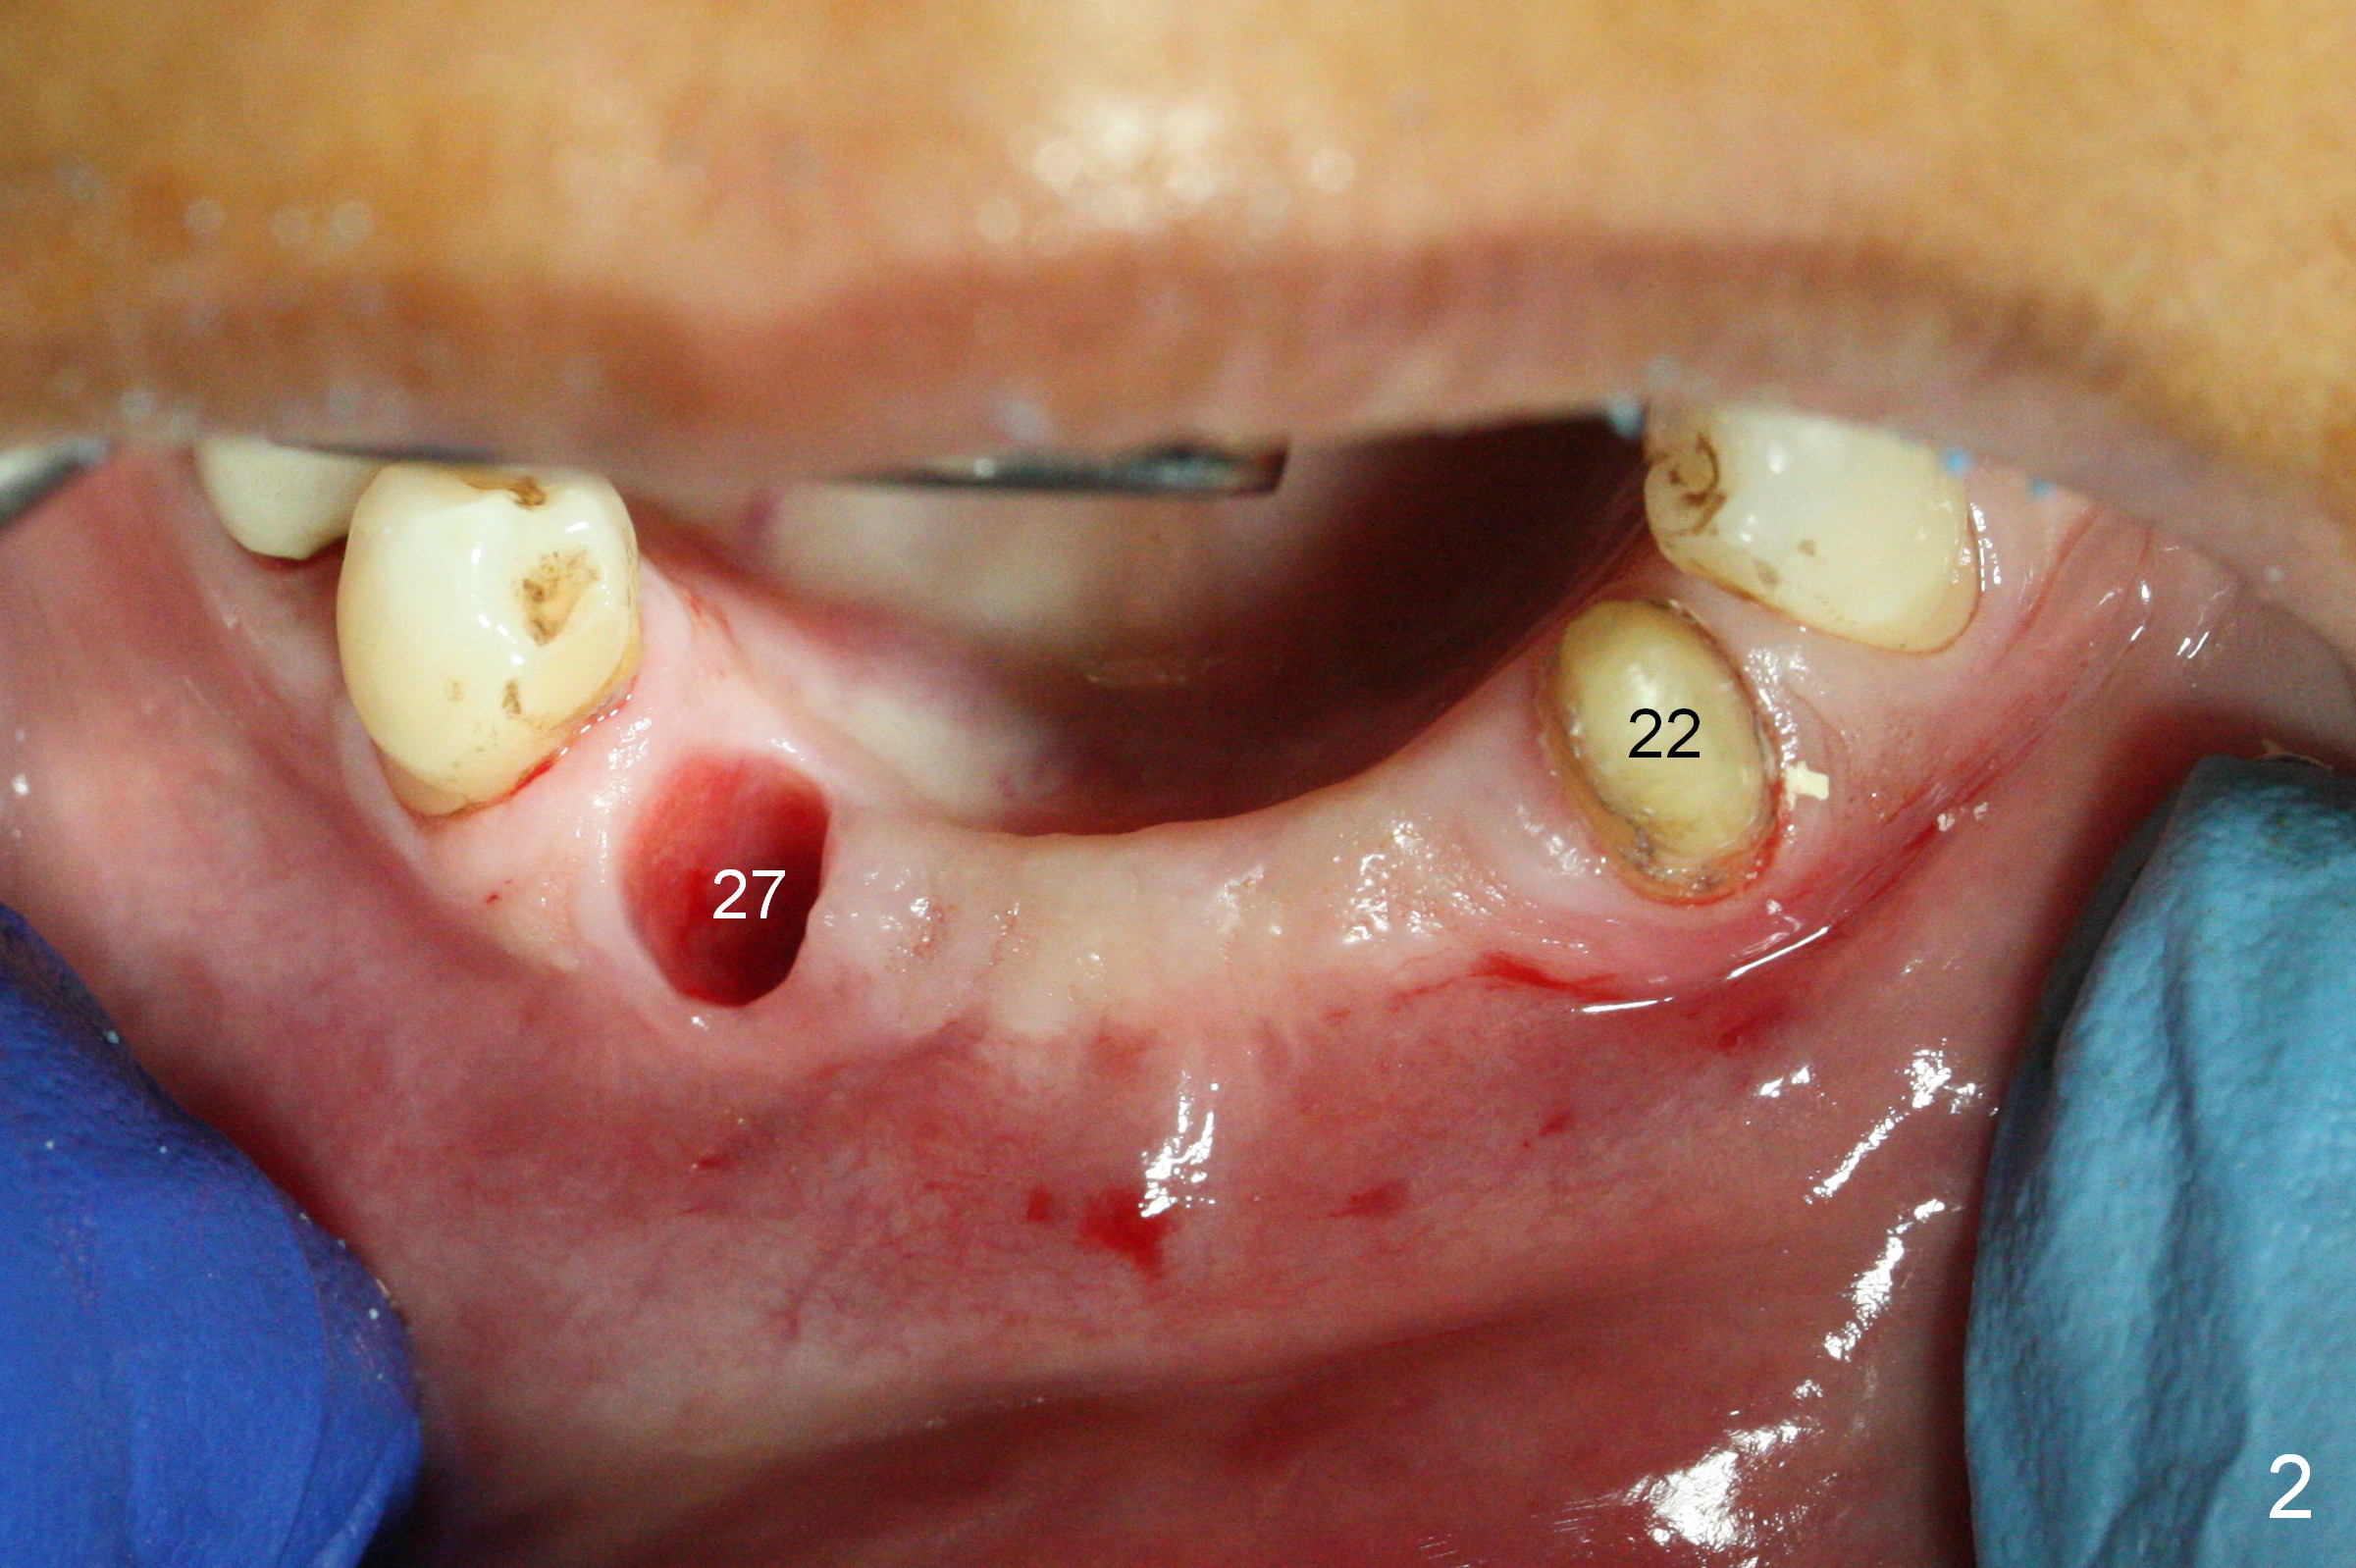

There is severe buccal gingival recession at #27 (Fig.1 arrow), as compared to that at #22. After removing the bridge and extraction of #27 (Fig.2 with severe loss of the buccal plate), a 3x18 mm drill is used to finish osteotomy (Fig.3). A 3.8x13 mm UF implant (Fig.3 green line) will be placed with 9 mm in the apparently solid, native (new) bone (blue line), while the coronal 5 mm will be occupied by the 5 mm cuff of a cemented abutment (pink line). The white dashed line is the gingival margin. The osteotomy is initiated as lingual as possible so that there will be at least 2 mm buccal gap when the narrow implant is placed. In spite of effort and precaution (guided surgery could control the trajetory), the coronal end of the implant tilts buccally so that a 4.5 mm 15 ° A 4 mm angled abutment is placed slightly subgingival (except buccal; Fig.5 A).

Since the ridge between the lower canines is atrophic (Fig.2), osteotomy starts at #23 and 25 after crestal reduction (Fig.4 arrowheads), Two of 2.5x12(4) mm 1-piece implants are placed (Fig.6). The implants at #23, 25 and 27 and the tooth #22 support an immediate provisional bridge (Fig.7).